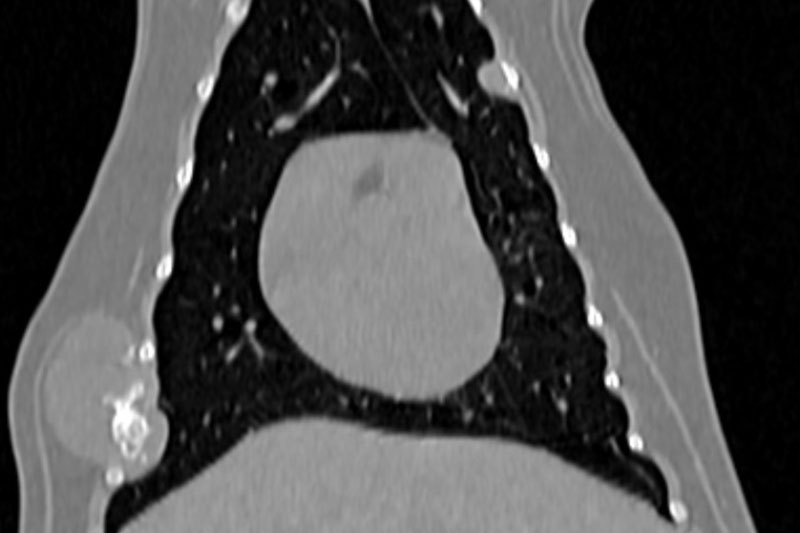

CT (Computed Tomography, 전산화 단층촬영) 검사는 X-ray를 이용해 반려동물의 몸을 여러 각도에서 촬영하고, 이를 컴퓨터로 합성하여 단면 이미지(슬라이스)를 만들어내는 정밀 진단 장비입니다.

사람 병원에서도 널리 사용하는 기술로, 뼈, 장기, 혈관, 종양 등 몸속 구조를 3차원(3D)으로 시각화할 수 있습니다.

| 흉부(가슴) | 폐종양, 늑골 골절, 기관지 협착, 심장 주변 병변 등 |

폐 질환의 상세 평가